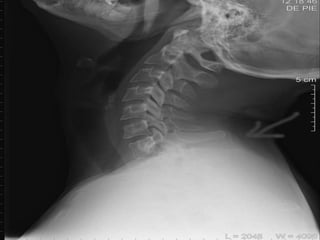

DIAGNOSTICO

Examen clínico y neurológico

La radiología simple

Las neuroimagenes (TC y RM)

Una vez estabilizado el paciente comienza la evolución diagnostica